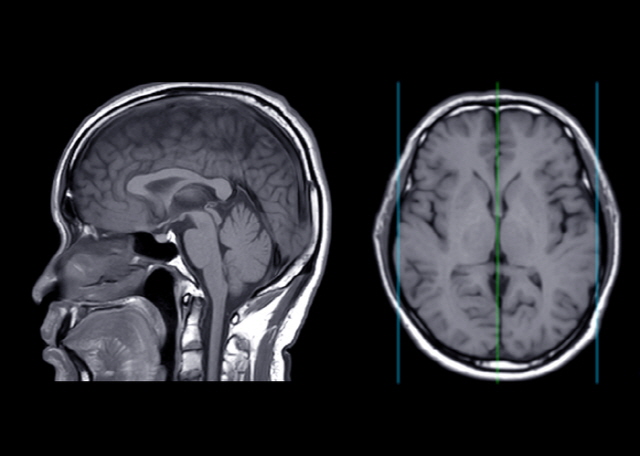

한국과학기술원(KAIST) 생명과학과 김찬혁·정원석 교수 연구팀은 세포 제거에 관련된 단백질을 인위적으로 조작해 알츠하이머를 유발하는 것으로 알려진 ‘베타 아밀로이드’표적으로 하는 새로운 융합단백질(Gas6)을 개발했다. 알츠하이머 쥐 모델 실혐 결과 Gas6는 뇌 속에 축적된 베타 아밀로이드 양을 현저하게 줄였고 손상된 인지능력·기억력이 기존 항체 치료제를 처방했을 때보다 높은 수준으로 회복하는 것이 확인됐다.